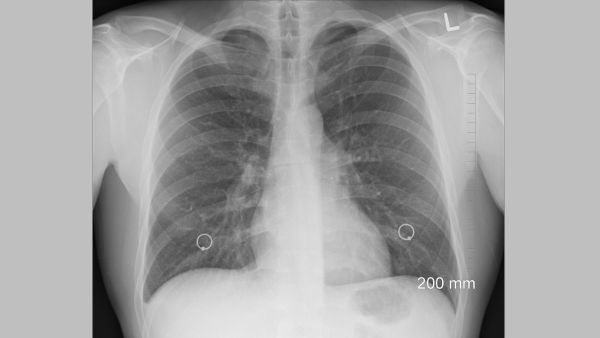

"వైట్ ఊపిరితిత్తుల సిండ్రోమ్" అనేది ఛాతీ X-కిరణాలపై తెల్లటి పాచెస్ కనిపించడం ద్వారా న్యుమోనియా యొక్క తీవ్రమైన రూపాన్ని వివరించడానికి ఉపయోగిస్తారు. ఈ పదం ఒక నిర్దిష్ట వ్యాధిని సూచిస్తున్నప్పటికీ, ఇది వాస్తవానికి అనేక వ్యాధుల లక్షణాలను కలిగిస్తుందని గమనించాలి.